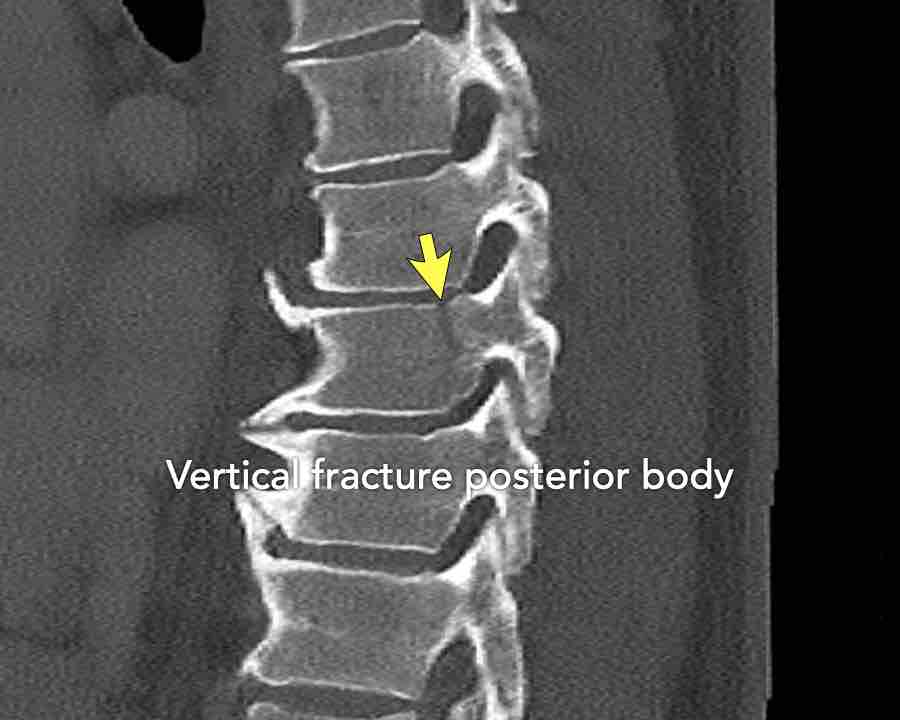

Findings:

- No C or B injury

- Fractures vertebral body with involvement of upper endplate (1 point) and posterior wall (2 points)

Conclusion

Injury type A3